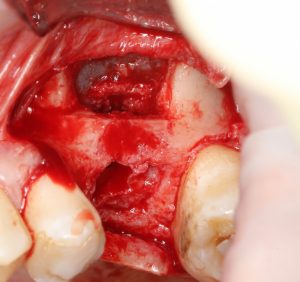

С другой стороны, существует определенная группа столяров-слесарей, живущих по принципу «посильнее закрутил — лучше держится» (то, что я называют «столярно-слесарным направлением в имплантологии»). Столяры-слесари, особенно 13 и 15 разрядов, с целью повышения первичной стабильности, игнорируют кортикальные фрезы и пытаются закрутить имплантат диаметром шейки 5.0 мм в лунку 3.7 мм, превышая крутящий момент в 2-3 раза. Ну, конечно, потом удивляются, почему на таких крутых имплантах и у таких крутых докторов возникает периимплантит:

В общем, если в ваши планы не входит лечение периимплантита и удаление отторгнувшихся имплантатов — не игнорируйте кортикальные фрезы. Никогда. Даже в III-IV биотипах кости. Почему — читайте здесь>> и здесь>>.

В общем, мы с вами не придурки слесари-столяры, периимплантита не хотим, поэтому кортикальные фрезы не игнорируем:

Кортикальная фреза погружается строго до отметки (см выше). В нашем клиническом случае (с синуслифтингом) это особенно важно, чтобы имплантат не улетел в субантральное пространство. Таким образом получаем лунку, полностью конгруэнтную будущему имплантату. Это очень-очень важно: